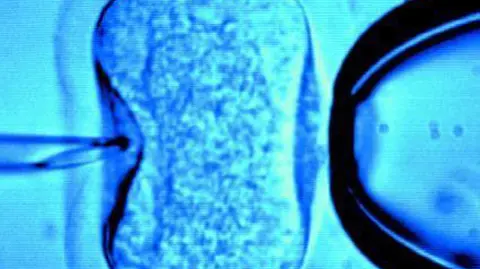

Arte e Ideas La biotecnología está próxima a crear óvulos a partir de células de piel Por León A. Martínez 06/09/2017 - 13:25

Política Urgen legislar sobre técnicas de reproducción humana asistida Por Notimex 13/08/2011 - 19:52

Política Experta urge legislar sobre reproducción asistida Por Redacción el Economista 06/10/2010 - 16:35